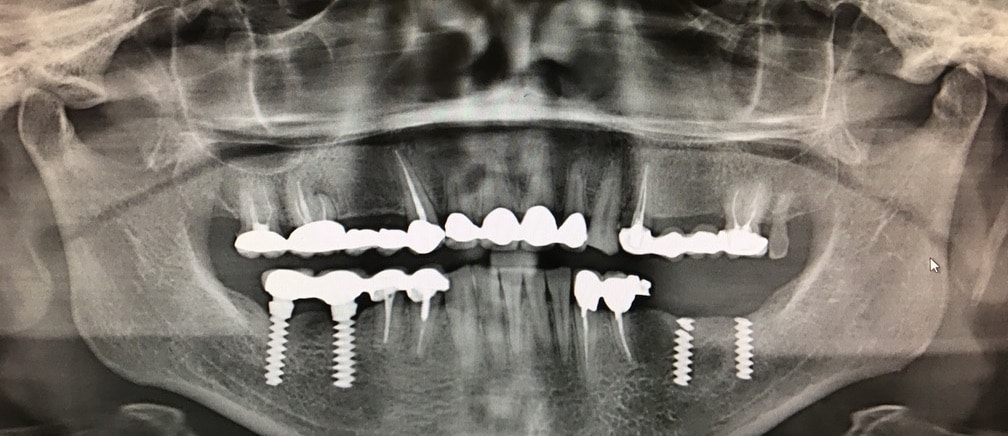

Final radiographic evaluation

Female, age 53. Good general and oral health status.

Presence of two broken implants in position 3.5 and 3.7

Aim of the work: removal of the 2 broken implants and fixed rehabilitation of the area